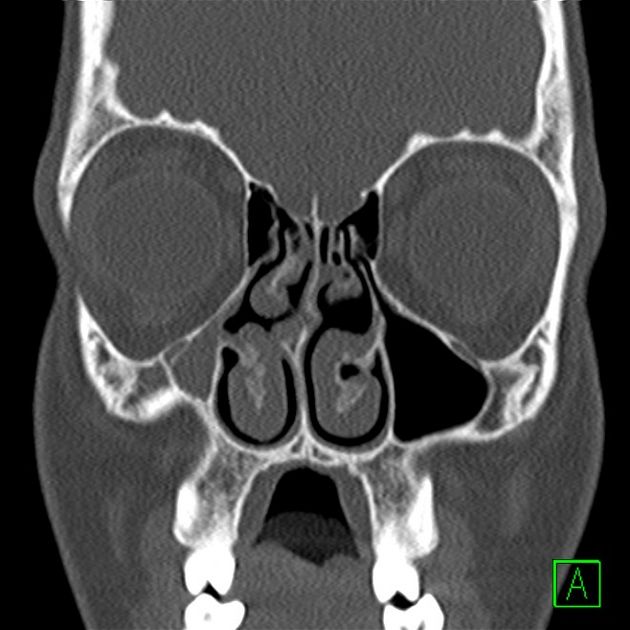

Il FUNGUS BALL:

Si tratta di una forma di sinusite cronica causata dall’accumulo di materiale fungino all’interno di un seno paranasale, più spesso il seno mascellare. Nella maggior parte dei casi, rimane confinato al seno senza invadere i tessuti circostanti.

I sintomi possono essere lievi o aspecifici e includono ostruzione nasale, secrezioni maleodoranti, dolore o senso di peso al volto, spesso da un solo lato. Talvolta la condizione viene scoperta casualmente durante esami radiologici.

La diagnosi si basa su TC dei seni paranasali, che mostra caratteristiche tipiche come aree iperdense all’interno del seno. Il trattamento è chirurgico e consiste nella rimozione del materiale fungino e nel ripristino della normale ventilazione del seno. Dopo l’intervento, la guarigione è generalmente completa senza necessità di terapia antifungina sistemica.